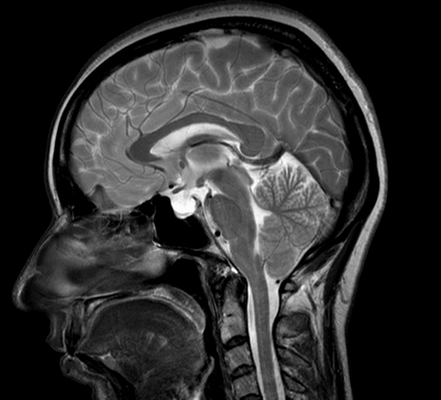

МРТ головного мозга. Сагиттальная Т1-зависимая МРТ. Липома и агенезия мозолистого тела.